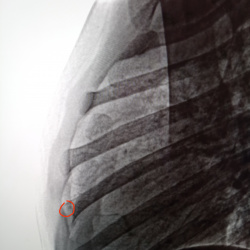

Коллеги, здравствуйте. Мужчина, 60. Анамнез неизвестен. Есть вопросы по плечевому суставу.

1) Красное - нет ли перелома акромиона? Смотрится максимально странно.

2) Желтое - это тендиноз...